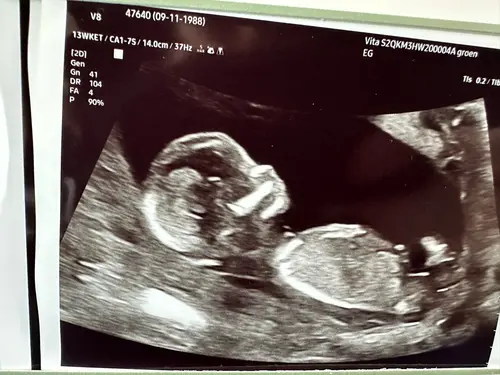

Hi, 12 weken nu. Heeft iemand een idee 😇🩷🩵